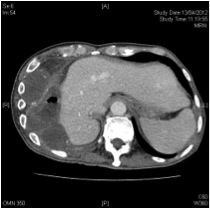

The team assessed the patient and reviewed all his medical history. This patient had repeated positive growth of ESBL E.coli from the respiratory tract which is uncommon cause of community acquired pneumonia. Moreover, the unresolved pneumonia might be related to the history of intra-abdominal operation which resulted in damage of the thoracic-abdominal barrier. The history of lung shadow also suggested a long existing lung problem. Therefore, we advanced the appointment of the CT scan of thorax and abdomen. (Picture 2) CT showed empyema necessitates in the right lower thorax with extension through the diaphragm and involvement of the abdominal wall. Finding was suggestive of long standing infection with disruption of the thoracic-abdominal barrier due to previous surgery. Barium follow-through showed mucosal irregularity in the hepatic flexure without definite communication to the right pleural cavity.